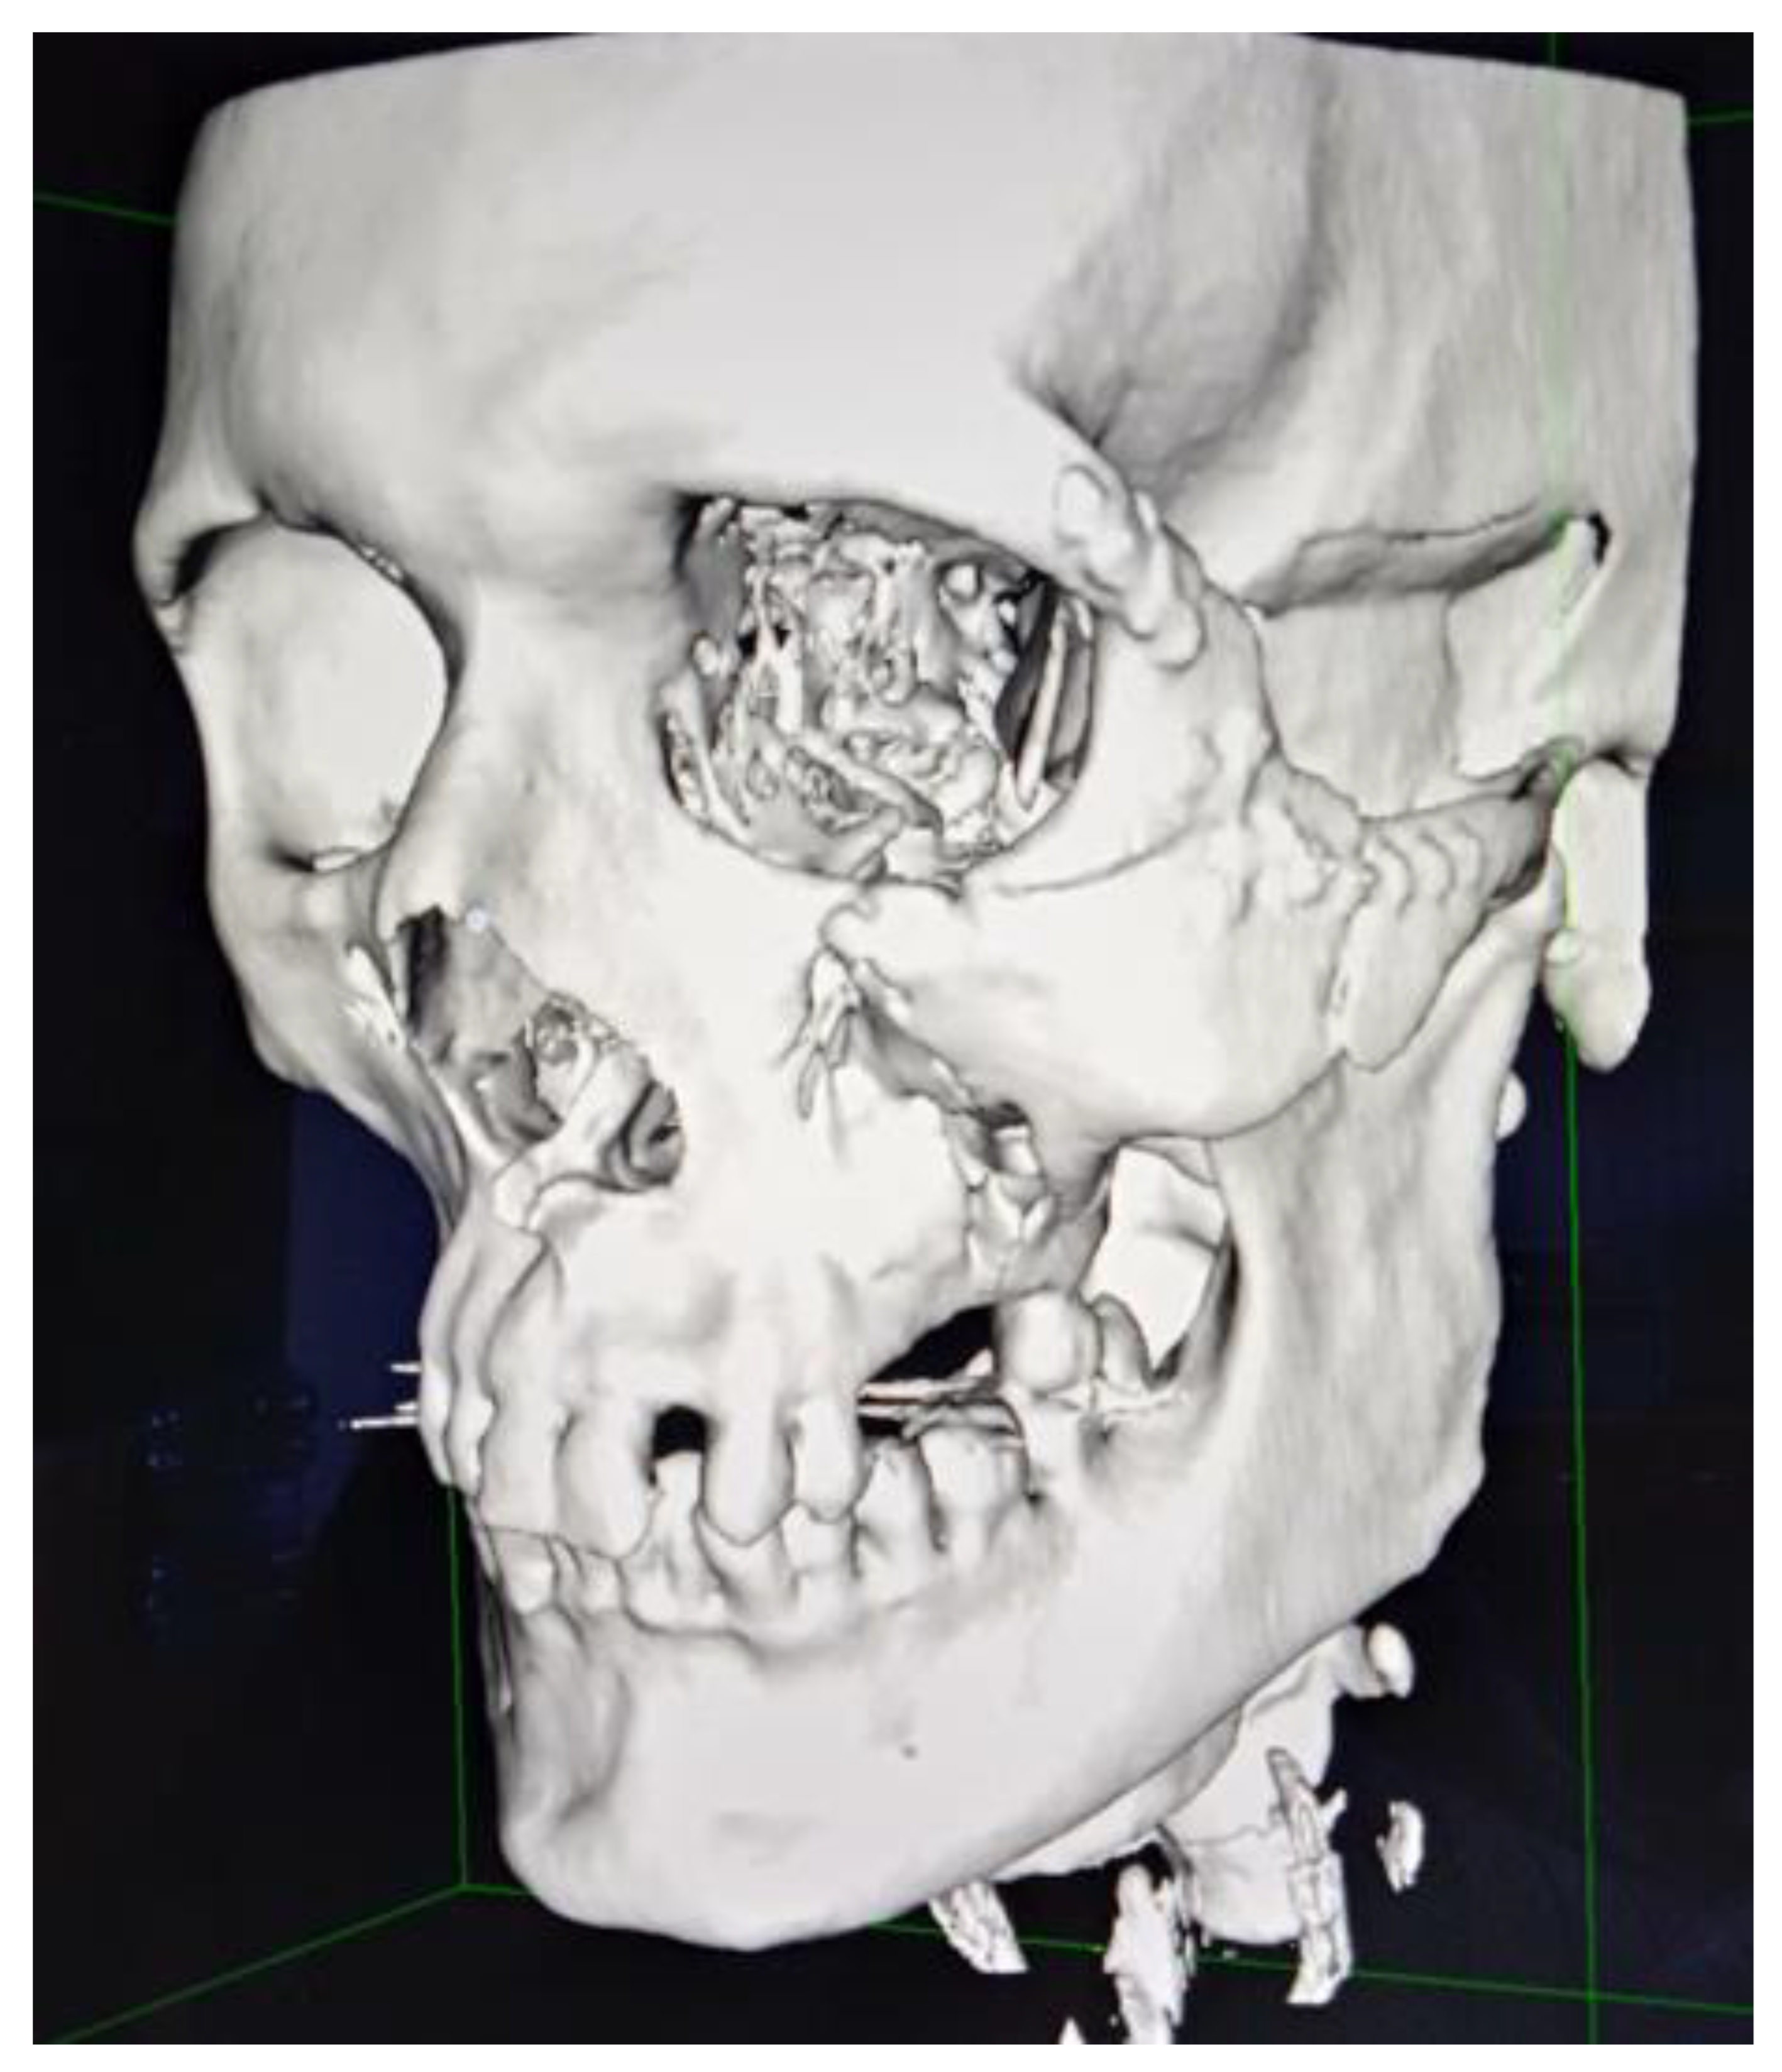

A 36 year-old male suffered from a blunt craniofacial trauma on the left temporal region caused by a baseball bat beating. The patient was admitted to the emergency department and then to the Ward of Maxillo-Facial Surgery. Because of the excessive fractures of the temporal bone along with the skull base and middle cranial fossa, the patient required intense monitoring (Figure 1, Figure 2, Figure 3, Figure 4, Figure 5 and Figure 6). Neurological status was fine; no CSF leak was present. No neurosurgical intervention to lift the displaced bone was used because of the close proximity of the meningeal artery in the fractured temporal bone region, which might cause serious, life-threatening bleeding. Secondly, the displacement was slightly less than 5 mm in total and symptomless. Detailed trauma-CT scans and 3D visualization revealed a fracture of the cranial base, along with the middle cranial fossa vault, cranial displacement of some part of the left frontal bone, and a fracture of the left zygomatic-orbital complex (Figure 7, Figure 8, Figure 9 and Figure 10).

Figure 3. Reconstruction from a 3D-CT trauma scan of the major cranio-facial fractures.

Figure 4. A frontal view on reconstruction from a 3D-CT trauma scan of the major cranio-facial fractures on the left orbital and zygomatico-malar complex area.